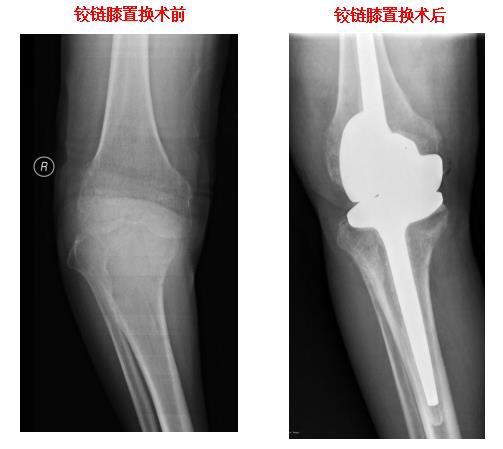

铰链膝置换

膝关节表面置换